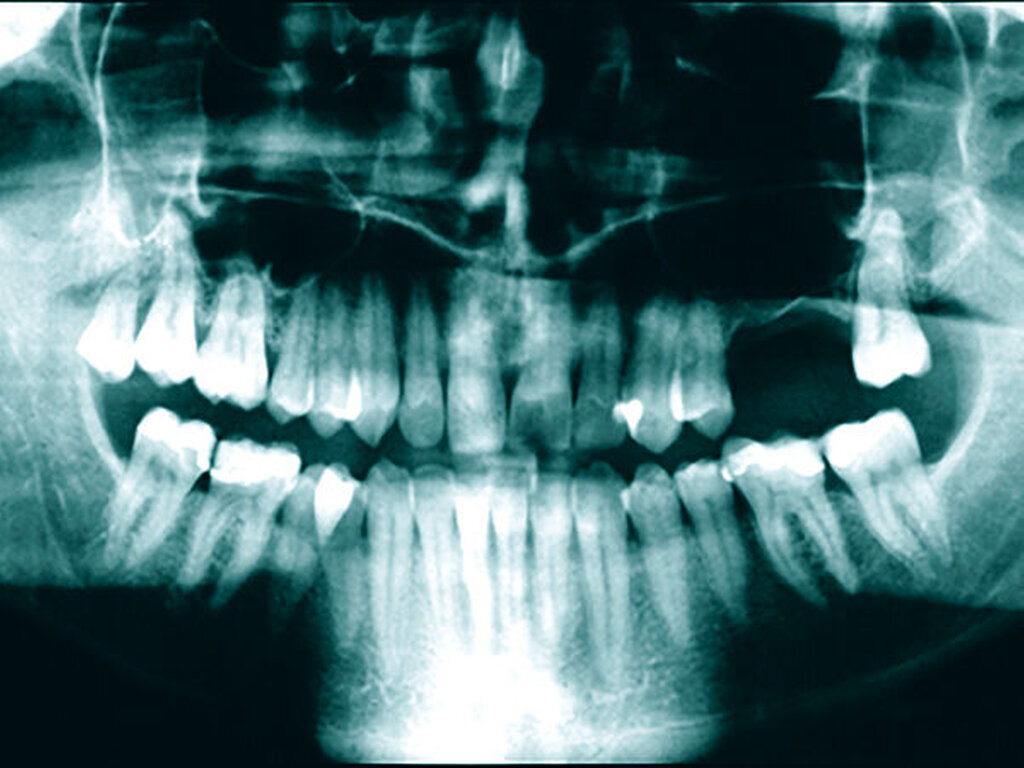

In der Zahnmedizin steht die oben beschriebene Homöopathie zwar nicht im Fokus, deren Weltbild kann aber als eine Art Einstieg in die alternativmedizinische Szene dienen. Sie kann dazu beitragen, sich weiteren alternativmedizinischen Modellen zu nähern, die ihrerseits für die Mundgesundheit gefährlich werden können, wenn sie beispielsweise zu drastischen invasiven Eingriffen mit irreversiblen Schäden motivieren. So gibt es Behandler, die auf der Grundlage sogenannter bioenergetischer Testmethoden (beispielsweise Muskeltests mit „Applied Kinesiology“) invasive Eingriffe wie Entfernungen intakter zahnärztlicher Versorgungen oder Zahnextraktionen (zuweilen sogar Serienextraktionen) vornehmen, unabhängig davon, ob die Versorgungen beziehungsweise Zähne nach aktuellem wissenschaftlichem Erkenntnisstand erhaltungswürdig sind oder nicht. Zahnärzte fräsen im Anschluss an Zahnextraktionen die Kieferknochen zur Beseitigung von vermeintlichen „Störfeldern“ aus und richten dabei erhebliche Schäden an (Abbildung 1).